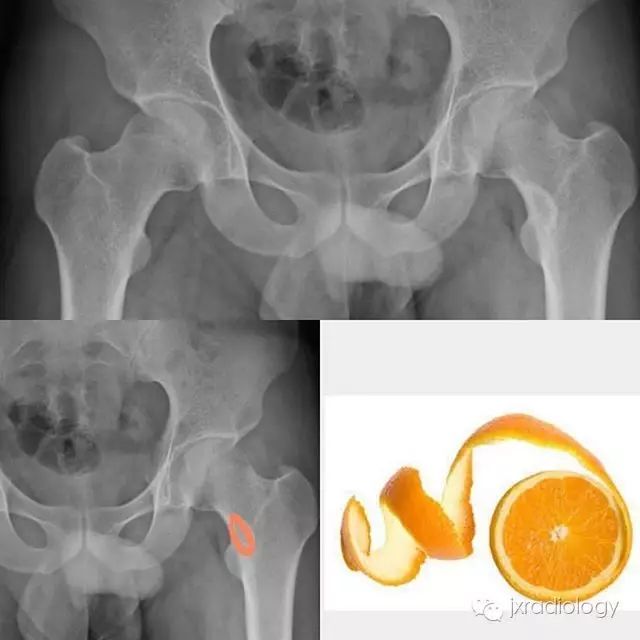

X线检查示骨纤维异常增殖症(Fibrous dysplasia ,FD)病变位于髓腔内,多见于骨干,病变区域多透亮,很少情况下出现高密度影(基质钙沉积时可出现),正常的骨小梁结构消失,代之以细颗粒“毛玻璃”样,有时病变周围的硬化骨带则可组成“果皮征”(rind sign)。

图示